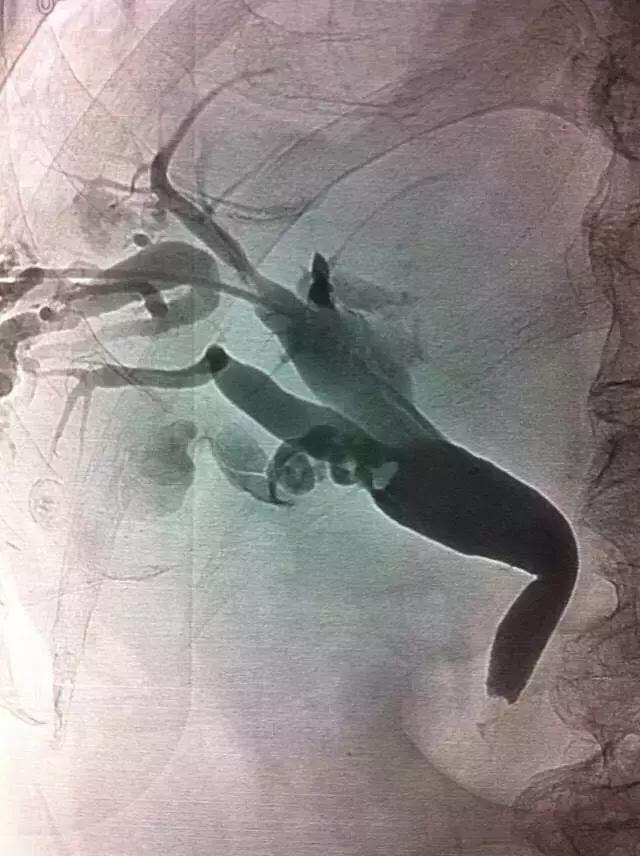

①内镜治疗。通过ERCP(经内镜逆行性胰胆管造影术)留置鼻胆管引流,通俗点说就是做胃镜,经十二指肠的胆管开口处置入引流管,解除胆道的梗阻,同时将结石取出,这种治疗方法创伤较小,术后恢复快,是一种比较理想的治疗方法